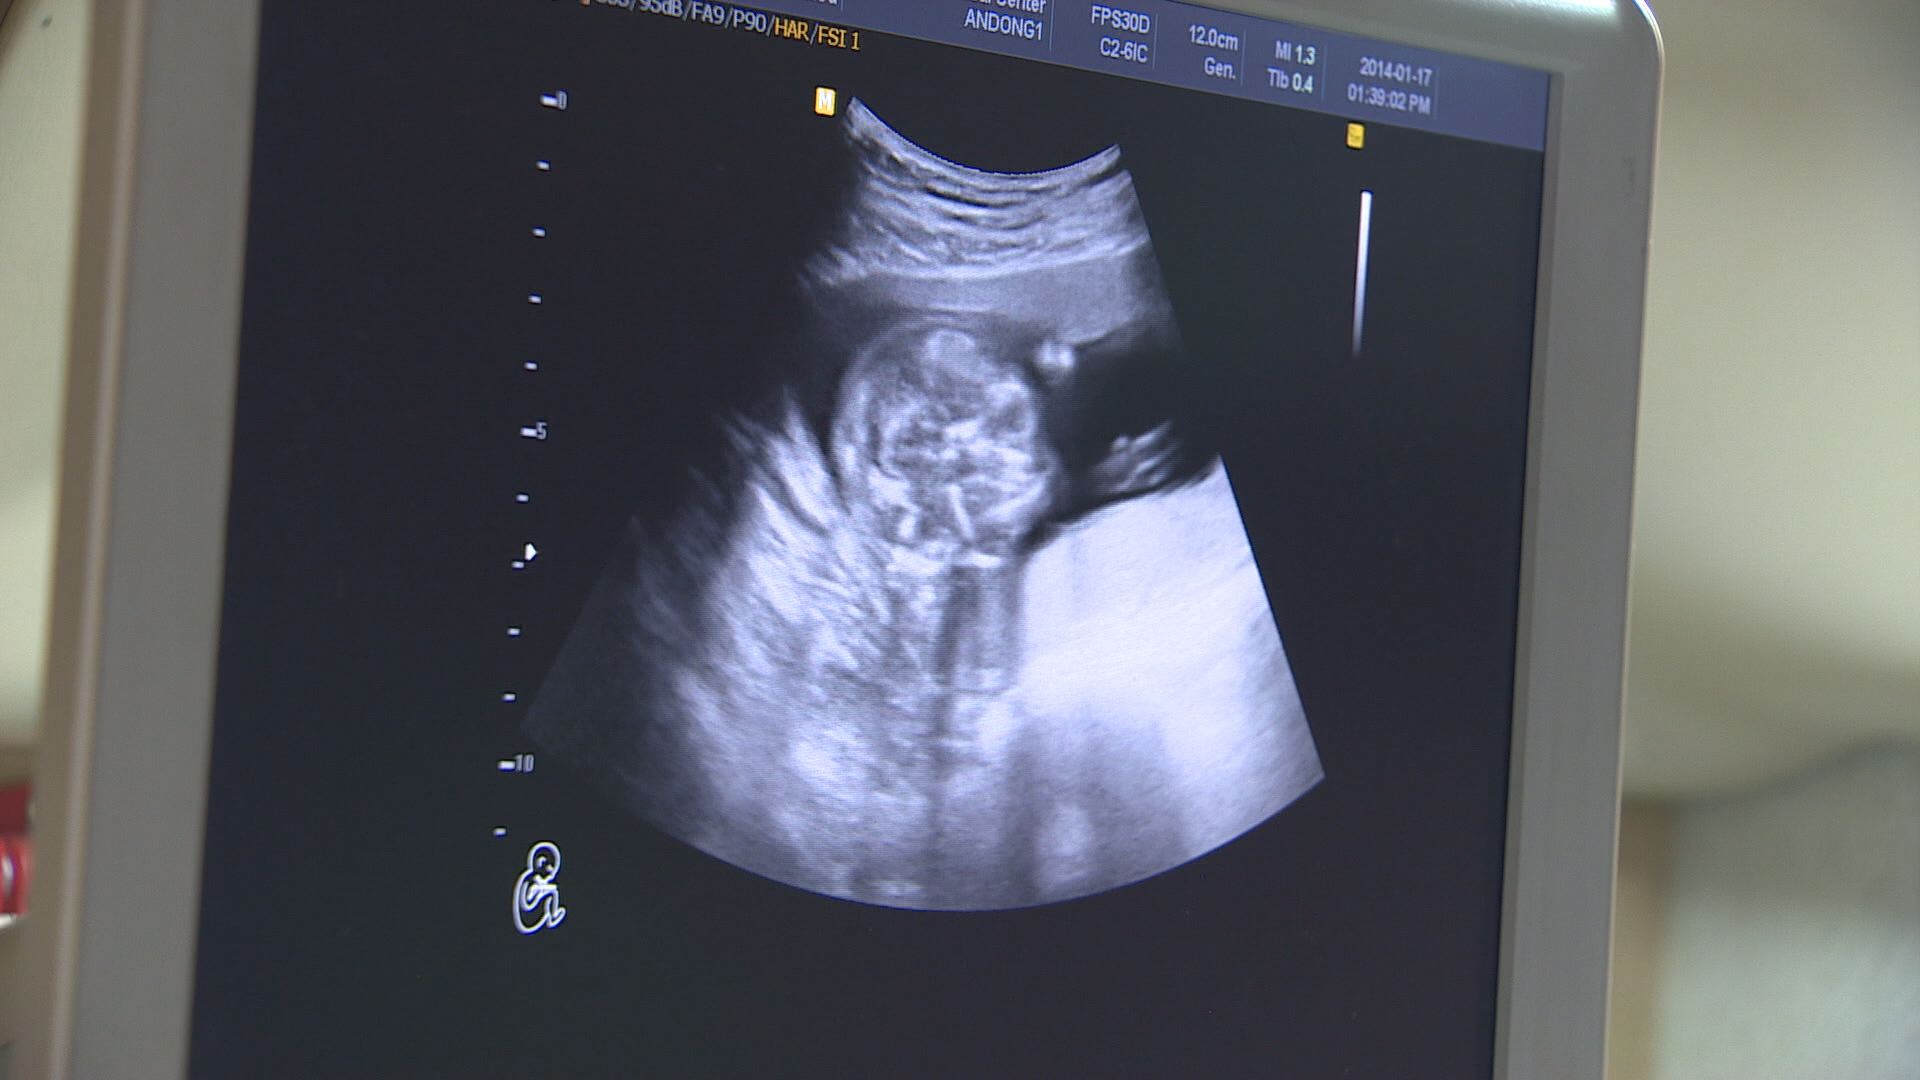

대구시는 기준 중위 소득 180% 이하 가정에만 했던 난임부부 시술비 지원을 2023년부터 모든 난임부부로 확대했습니다.

또 기준 중위 소득 150% 이하만 지원했던 산모·신생아 건강관리 비용도 2023년부터 기준을 없애고 모든 출산가정에 지원합니다.

산모와 신생아 건강 관리사가 출산 가정을 방문해서 산후 관리와 신생아 양육을 도와주는데요.

보건소를 방문하거나 온라인으로 서비스를 신청할 수 있습니다.

저출생 문제가 심각하기 때문인데요.

2022년 1월부터 9월까지 대구 출생아는 7,700여 명으로 전년도 같은 기간 8,200여 명과 비교해 6.1% 줄었습니다.

"기존의 소득 제한 기준을 폐지함으로써 모든 난임부부와 출산 가정이 혜택을 보게 됩니다."